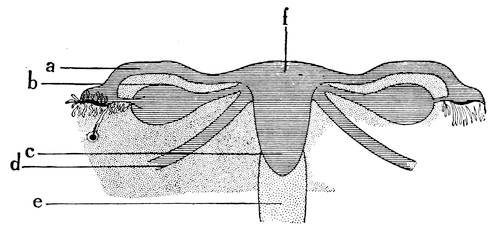

Mons of Venus, labia majora, minora, vestibule, bulbs, clitoris, Bartholinian glands, hymen, vagina, uterus, broad and round ligaments, viiitubes, ovaries, Graafian follicle, ovum.

Function of ovaries, ovum, Graafian follicle, tubes, menstruation, function of uterus, female ejaculation, function of vagina, Bartholinian glands, of clitoris, course of the sexual act.

When the Wolffian body has almost reached its greatest development a second longitudinal duct makes its appearance by the evagination of the ventral surface of the Wolffian body. These ducts lie in close proximity of the Wolffian ducts, along the dorsal aspect of the coelom, or body-cavity, and are known as the ducts of Müller, or the primitive female ducts. The function of these canals in lowly organized animals is that of receiving21 from the body-cavity the ova and of evacuating them from22 the body. The Müllerian ducts also open into the cloaca. At the lower end the Müllerian and Wolffian ducts run in close apposition and form the genital cord. At this stage of development the embryo is thus hermaphroditic like the worms.

At the caudal end, the Müllerian ducts fuse together into

one, the walls, along the entire line of the union, degenerate,

and the two ducts thus form a single duct, the later vagina and

uterus. Until the fifth month there is no distinction between25

26

vagina and uterus, the two organs form a single sac-like structure.

At the beginning of the fifth month, a circular ridge in

the wall of the sac makes its appearance and marks the division

between the vagina and the uterus. When the lower portion of

the two Müllerian ducts have fused to form a single canal, the

utero-vaginal sac, the lumen of the vagina is still obliterated,

being filled with epithelial cells. By the breaking down of the

central epithelial cells, the cavity is established.

At this period a little semicircular crescentic fold attached to the dorsal margin of the aperture of the vagina arises and forms the hymen, an organ which has always played such an important rôle in the fancy of all nations.

The upper blind ends of the Müllerian ducts, with their expanded funnel-shaped mouths, diverge and form the oviducts, or the Fallopian tubes.

In the female the vestibule, or the shallow depression which was formed through the breaking through of the urogenital membrane, remains open throughout life, and is termed the vestibule of the vulva. From the sides of the lower part of the sinus a pair of evaginations are formed and give rise to the Bartholinian glands. The vestibule being in fact the open sinus urogenitalis, the urethra and the vagina naturally have their orifices in the same.

The genital tubercle ceases to grow in the female and becomes the clitoris. The genital folds or the lips of the vestibule become prolonged and form the labia minora or the nymphae. The genital swelling increases in size through adipose and fibrous tissue. The part situated on the ventral side of the clitoris becomes the mons veneris, while the lateral parts are converted into the labia majora of the vulva.